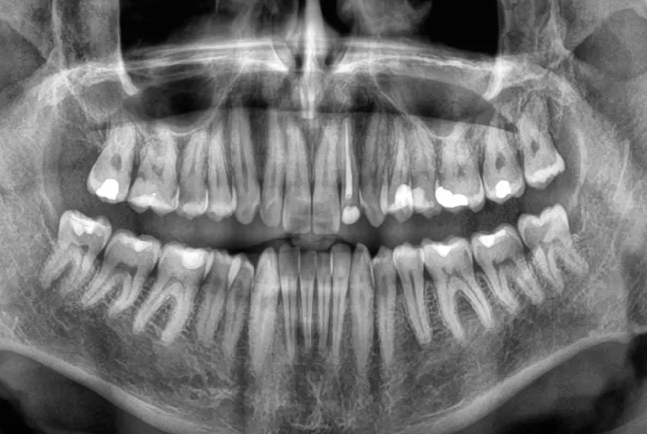

Diş itkisi ölüm riskini artıra bilər -ARAŞDIRMA

Diş itkisi ölüm riskini artıra bilər -ARAŞDIRMAYeni bir araşdırma göstərib ki, yaşlı insanlarda dişlərin sürətlə itirilməsi ölüm riskinin artması ilə əlaqəlidir. Çinli alimlər 3,5 il ərzində 8073 yaşlı insanı izləyərək belə nəticəyə gəliblər.

Lent.az "sciencealert.com" portalına istinadla xəbər verir ki, tədqiqatın nəticələrinə görə, dişlərin itirilmə sürəti nə qədər yüksəkdirsə, bütün səbəblərdən ölüm riski də bir o qədər artır. Bu əlaqə yaş, cins, təhsil, içki və məşq vərdişləri kimi digər amillər nəzərə alındıqdan sonra da qalır. Mütəxəssislər bildirirlər ki, dişlərin itirilməsi birbaşa ölümə səbəb olmur, lakin diş itkisinə yol açan sağlamlıq problemləri, məsələn, iltihab, pis qidalanma və ürək xəstəlikləri ömrü qısalda bilər. Alimlər diş itkisinin insanın ümumi sağlamlıq vəziyyətini qiymətləndirmək üçün göstərici kimi istifadə oluna biləcəyini vurğulayırlar. Həkimlər dişlərin qorunması üçün müntəzəm diş həkimi müayinəsini, gündə iki dəfə fırçalamağı və siqaretdən uzaq durmağı tövsiyə edirlər.

Araşdırma "BMC Geriatrics" jurnalında dərc olunub.